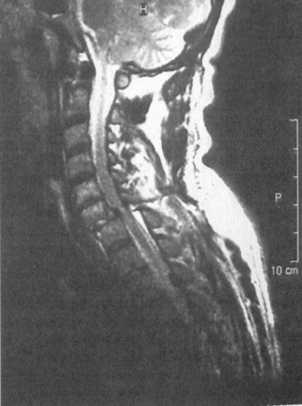

Ценную информацию о состоянии вывихнутых позвонков и спинного мозга дает

МРТ (рис. 2.6, 2.7). МРТ позволяет определить наличие зон ишемии в спинном

мозге (рис. 2.8, 2.9), состояние ликвородинамики (рис. 2.10).

Рис. 2.10. Компрессионный перелом С6 позвонка со смещением его

кзади

и нарушением ликвороциркуляции на данном уровне